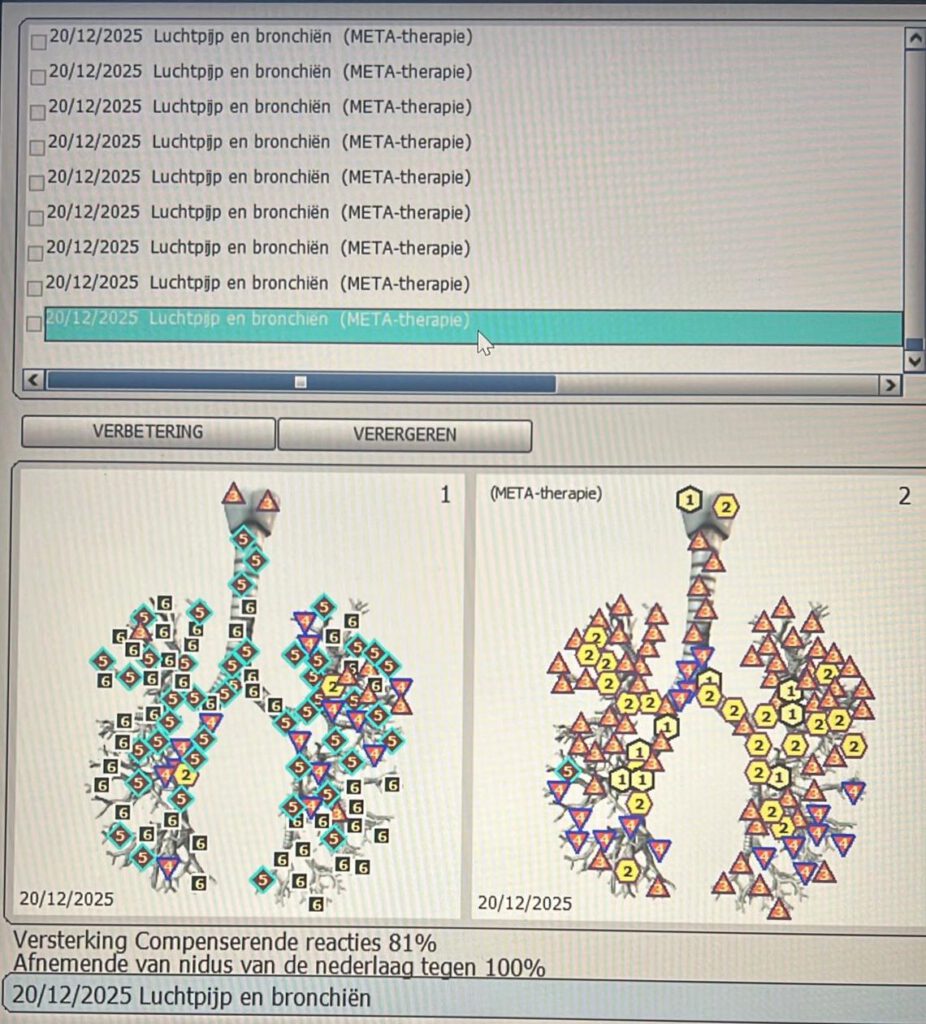

Links zie je weer de zelfde luchtpijp en bronchiën, maar dan na de behandeling met meta-therapie

Je ziet hier dus een behoorlijke verbetering.

Er is slechts 1 vijf nog te zien, een aantal vieren maar ook behoorlijk wat drieën en tweeën, een behoorlijke verbetering dus wat we behaald hebben!

Hieronder zie je nog in percentages de verzwakking aan de linkerkant (dus met bacterie) en de versterking aan de rechterkant na behandeling met meta-therapie.

De verzwakking is 29%, de versterking is 81%, dus totaal een verbetering van maar liefst 110%.